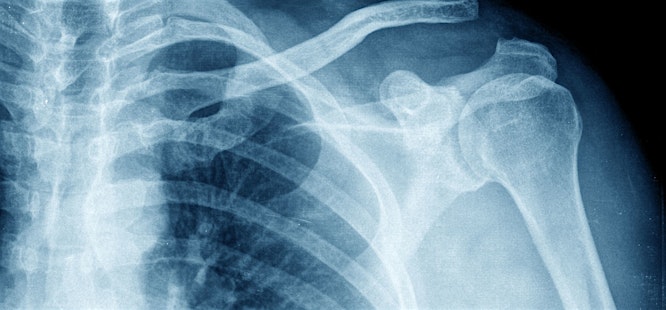

At urgent care clinics, providers most commonly order bone or chest X-rays. Bone X-rays can be targeted at any part of the skeleton, including arms, legs, the spine, or the skull. Bone X-rays are excellent for showing the integrity of the bone structure, the alignment of bones, and the presence of any cracks, breaks, or other abnormalities in the bone tissue.

If your urgent care doctor suspects a fracture, your provider will order multiple images from different angles to obtain a comprehensive view of your bone. On an X-ray, normal bones appear as a continuous line or pattern. A fracture is seen as a distinct break or crack in this pattern.